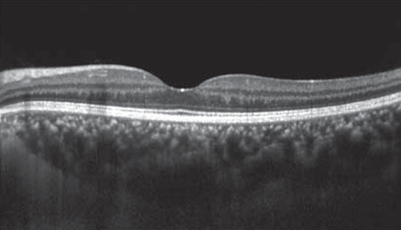

網膜は層構造になっており、その層構造を断面的に観察する検査です。

脈絡膜新生血管や浮腫の状態がわかります。